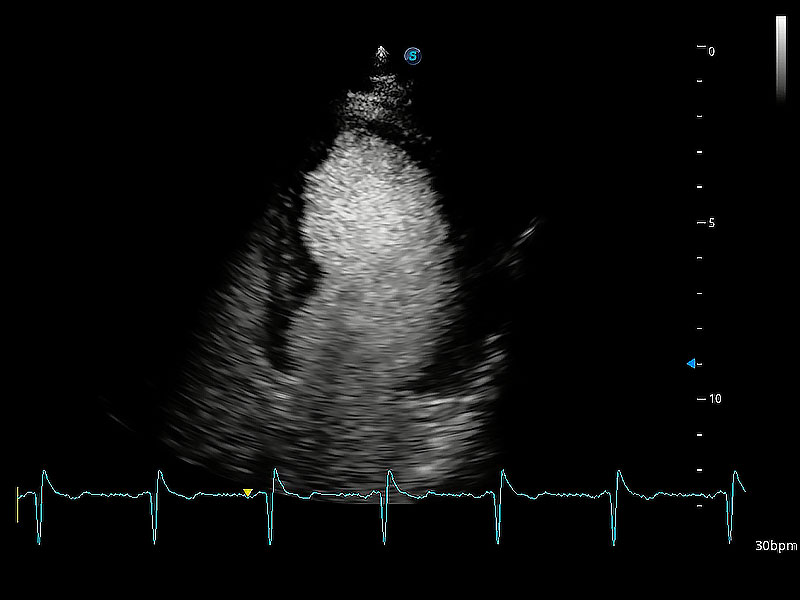

ProPet 80 配备了丰富的心脏探头群、先进的成像技术和专业的心脏测量工具,可帮助动物医生为不同体型和生理结构的动物提供心脏和心肌功能的全面评估。

通过心肌识别技术与二维斑点追踪技术相结合,对心脏的超声图像进行量化分析。计算心肌17个节段的应变、应变率、速度、位移等,并通过牛眼图的形式进行呈现。

通过360度任意调节3条M型取样线,在同一心动周期上观察心脏不同位置的运动曲线,得到准确的心功能测量数据,有效评估心肌运动及左心室功能。